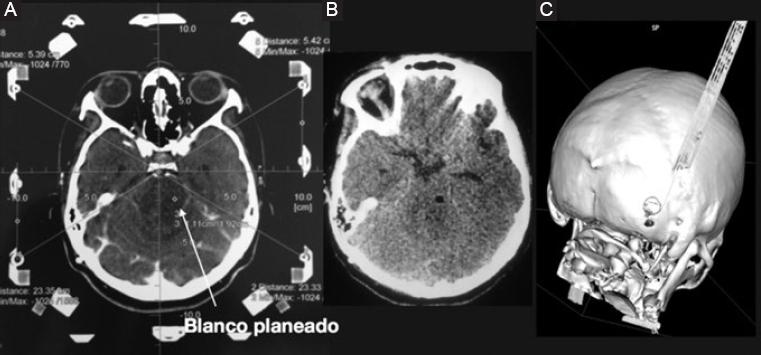

En todos los casos el paciente salió de la sala de operaciones directo a un estudio de tomografía simple de cráneo y a la sala de recuperación (Figs. 2 y 3).

Figura 3 Se muestra otro caso de la serie que resultó tener un astrocitoma difuso. A: Tomografía contrastada de cráneo con fiduciales del sistema CRW que muestra el sitio planeado para el blanco (flecha). B: Sitio con burbuja de aire que indica el sitio de toma de biopsia. C: Reconstrucción tridimensional de una tomografía posoperatoria que muestra el trépano hacia la fosa posterior.